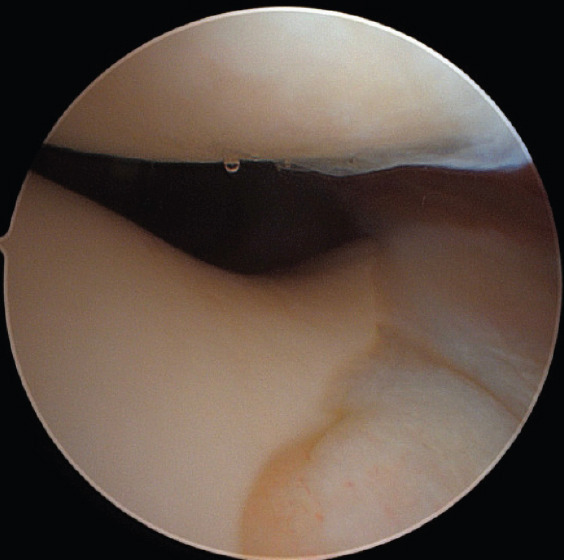

Case report: Our patient is a 38-year-old female who presented to the outpatient orthopedic clinic complaining of right knee pain in the setting of a traumatic kneeling event. She had a past medical history of asthma, polycystic ovary syndrome, and anxiety, but no surgical history related to the knee. She underwent magnetic resonance imaging identified what appeared to be a bucket-handle medial meniscus tear. The patient was brought to the operating room where diagnostic arthroscopy revealed a radial tear at the posterior horn of the medial meniscus as well as an anomalous connection between the anterior and posterior roots. The band specifically ran from the posterior horn of the medial meniscus, then superiorly and along the posterior cruciate ligament, and ultimately attached to the anterior horn of the medial meniscus in an "O" shape. In addition, a large patellofemoral plica was identified overlying the lateral femoral condyle. The tear, plica, and anomalous band were all debrided. The patient was progressing well on her most recent 7-month follow-up visit.